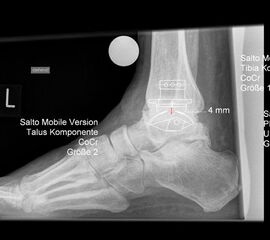

• Prothesenplanung anhand von Röntgenschablonen (Abb. 1 und 2).